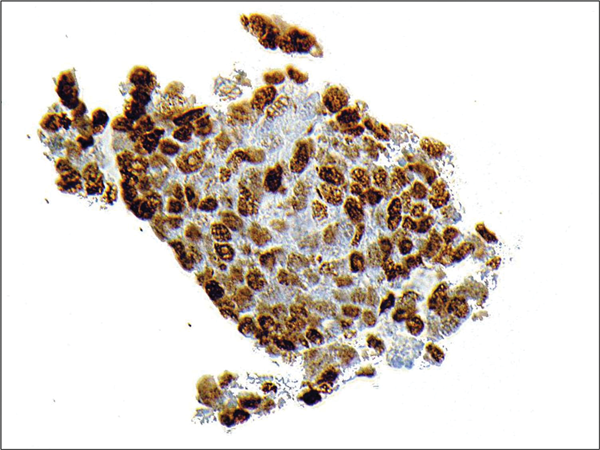

Figure 6: TTF-1 immunohistochemistry showing strong nuclear

staining with antibodies to thyroid transcription factor 1.